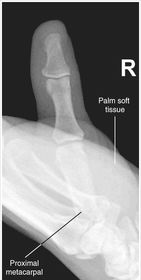

| AP Thumb Criteria | ANATOMY: entire digit including trapezium CRITERIA: equal concavity on both sides of digit open joint spaces no superimposition from adjacent bones POSITIONING: CR perpendicular @ 1st MCP joint |

| Oblique Thumb | ANATOMY: entire digit including trapezium CRITERIA: more concave to the side farthest from IR open joint spaces no superimposition from adjacent bones POSITIONING: CR perpendicular @ 1st MCP joint |

| Lateral Thumb | ANATOMY: entire digit including trapezium CRITERIA: most concave to one side, while the other is straight open joint spaces no superimposition from adjacent bones POSITIONING: CR perpendicular @ 1st MCP joint |

| AP Thumb | metacarpals overlapping thumb |

| Oblique Thumb | slightly overrotated foreshortened distal phalanx |

| Lateral Thumbs | should be concave to one side only and straight on the other images are not truly lateral |